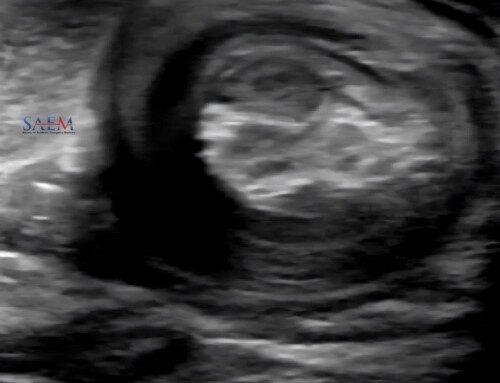

This component emphasizes clinical cases in which ultrasound proved useful for diagnosis (similar to the #US4TW series).

- A clinical case is provided to the learner with an associated ultrasound clip. The learner can then reflect on the differential diagnosis and further work-up prior to clicking the drop down button to reveal the answer and learning point.

Example of the “Clinical Application” Component of the EM Ultrasound website.